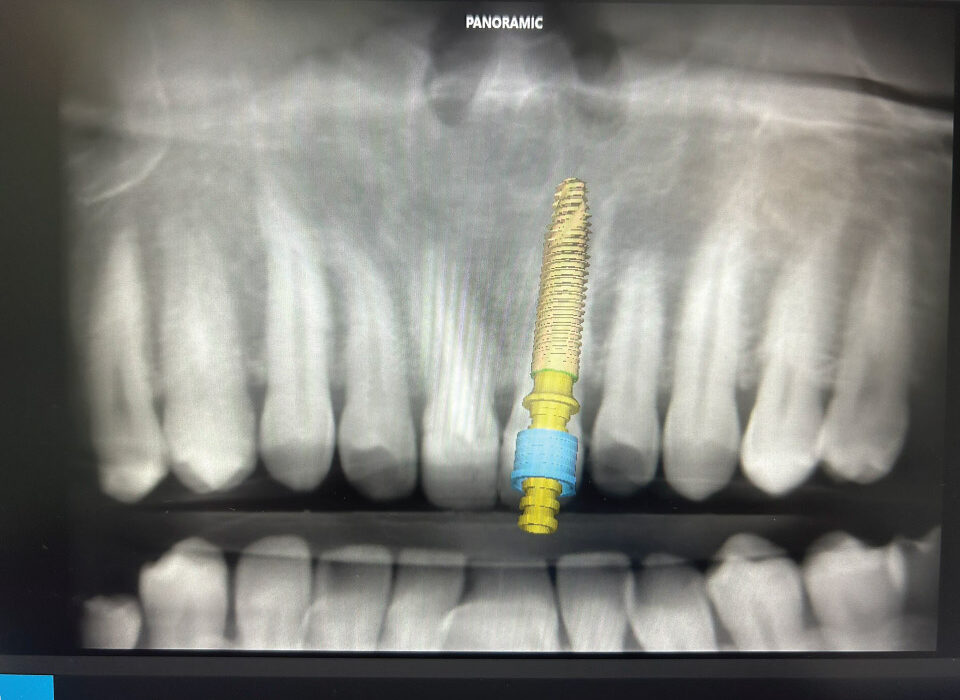

Surgical Guides

Surgical Guide is a digital tool that ensures accurate positioning and angulation of implants, which is crucial for the success and longevity of the implant. We fabricate different types of surgical guides, including tooth-borne, mucosa-borne, and bone-borne guides i.e stackable.